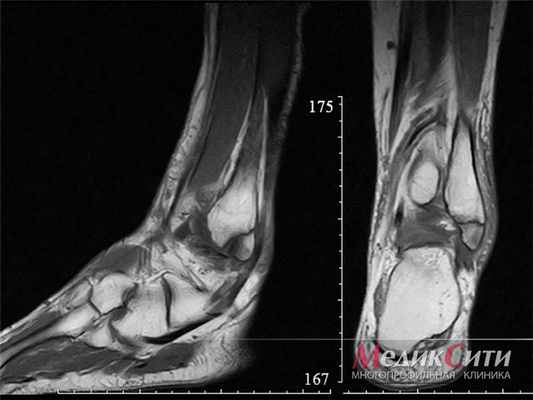

МРТ голеностопа: перелом лодыжки

(Слева) При МРТ в сагиттальной плоскости на Т1ВИ вдоль ладонной поверхности пястно-фалангового сустава определяется образование с неровным нечетким контуром. Образование характеризуется изоинтенсивным сигналом по сравнению с мышцами и наличием гипоинтенсивных очагов. Следует отметить, что у этого ребенка открыта зона роста.

(Справа) При МРТ в сагиттальной плоскости на Т2ВИ в режиме FS выявленное инфильтративное образование характеризуется гетерогенно гиперинтенсивным сигналом и наличием рассеянных гипоинтенсивных очагов, соответствующих кальцификатам.